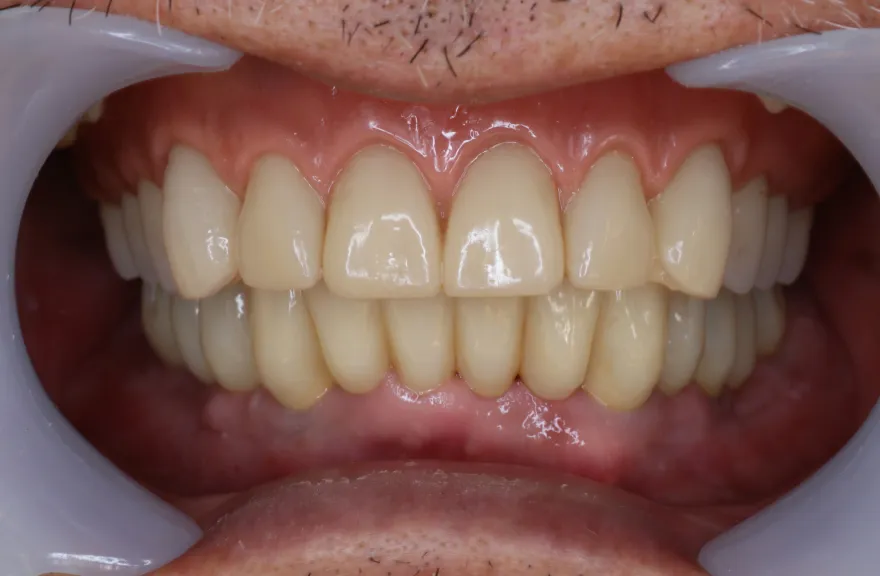

写真の通りに治療を終了いたしました。

上顎は総義歯の形態に、下顎は十分な寿命を持った歯は残して、長期的な保存が難しい歯はインプラント治療を施しました。上顎を総義歯形態にすることにより、何かが起こっても義歯の修理を行えば対応が可能です。即日の修理・完了も難しくないでしょう。

下顎は十分な寿命を持った歯しか残していないので、今後の人生でよっぽどのことがない限りトラブルが起きないと考えます。インプラント治療を施してある部分も、同様にトラブルが起きにくいと考えています。歯周病になった、とか歯が欠けた、というインプラント治療の悪い面が聞こえてくるようになりましたが、噛み合う上の歯を総義歯とすることで、過大な力がかかることなく、トラブルが起きにくい結果を得ることができました。

上顎は総義歯ですが、『今まで食べられなかったものがなんでも噛めるようになった』と、患者さんよりお言葉を頂戴しております。